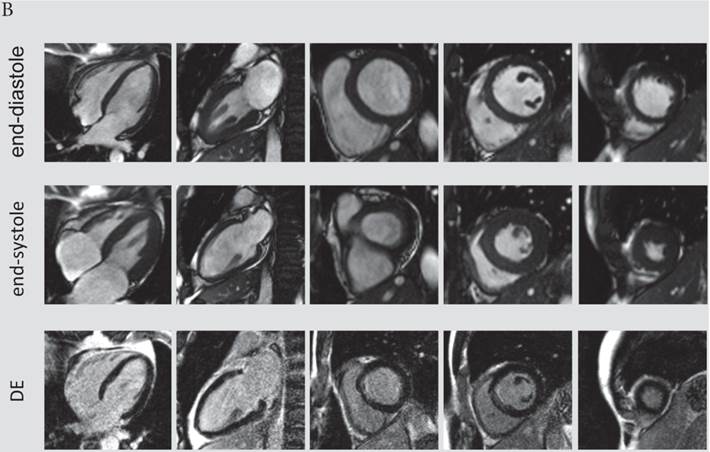

The presence and extent of microvascular obstruction on DE-CMR was significantly correlated to QTd-Rrel (r=-0.725, p<0.001 and r=-0.719, p<0.001), respectively. Patients in the 1st tertile of QTd-Rrel had the highest prevalence (69%) and extent of microvascular obstruction (4.1% of LV mass), and patients in the third tertile of QTd-Rrel showed the lowest (0%). A typical CMR scan of patients with low and high QTd-Rrel post revascularization is shown in figure 3a and 3b.

Figure 3

A) CMR scan of an 63-year-old male exhibiting only a minor reduction of QTd-Rrel post revascularization (QTd-Rrel 1st tertile). This patient had extensive, predominantly transmural myocardial infarction (average infarct transmurality: 95%, QTd-Rrel :0%) with presence of microvascular obstruction. B) A typical CMR scan of a patient with high reduction QTd-Rrel . This 60-year-old male was categorized to the 3rd tertile of QTd-Rrel . CMR images showed limited, non-transmural infarction (average infarct transmurality: 22%, QTd-Rrel: 80%).